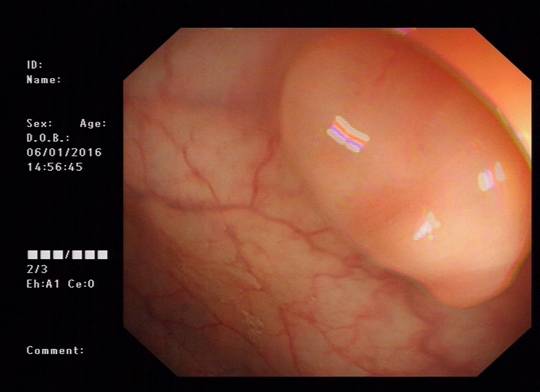

我院引进高端奥林巴斯电子胃肠镜

近日,我院引进日本奥林巴斯电子胃肠镜最新机型CV-290型,现已正式投入使用。

据悉,该款电子胃肠镜系日本奥林巴斯最新机型,具有窄波成像(NBI)、IHB色彩强调、构造强调、轮廓强调、自动增益、快速实时冻结等功能,超高解析度的图像输出、超大视野角度及高清超大医用显示屏,图像显示如实物般高保真色彩,使镜子就像内镜医生火眼金睛的延伸,看清患者胃肠道的真实病变情况,可最大程度的提高诊断及治疗的准确率,尤其在胃肠道早癌筛查及治疗方面最具优势。

图:清晰的镜下图像

另外,该款机型拥有USB接口,能随时输出检查图片信息,用于临床科研及教学;拥有原装水泵、气泵装置,可满足检查、治疗等不同需要;该款机胃镜插入部外径9.9毫米、肠镜插入部外径11.3毫米,这种超细、硬度可变的特质,使患者检查感受更为舒适.